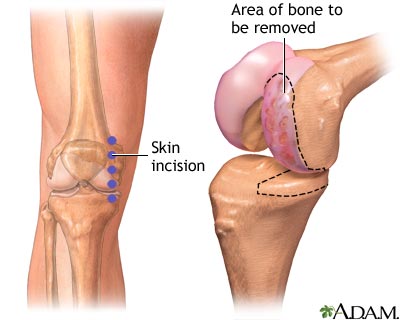

Partial knee replacement surgery removes damaged tissue and bone in the knee joint. It is done when arthritis is affecting primarily only one part of the knee. The areas are replaced with an artificial implant, called a prosthetic. The rest of your knee is preserved. Partial knee replacements are most often done with smaller incisions, so there is less recovery time.

The surgeon will make a cut over your knee. This cut is about 3 to 5 inches (8 to 13 centimeters) long.

- Next, the surgeon looks at the entire knee joint. If there is damage to more than one part of your knee, you may need a total knee replacement. Most of the time this is not needed, because tests done before the procedure would have shown this damage.

- The damaged bone and tissue are removed.

Partial knee replacement - series

Presentation